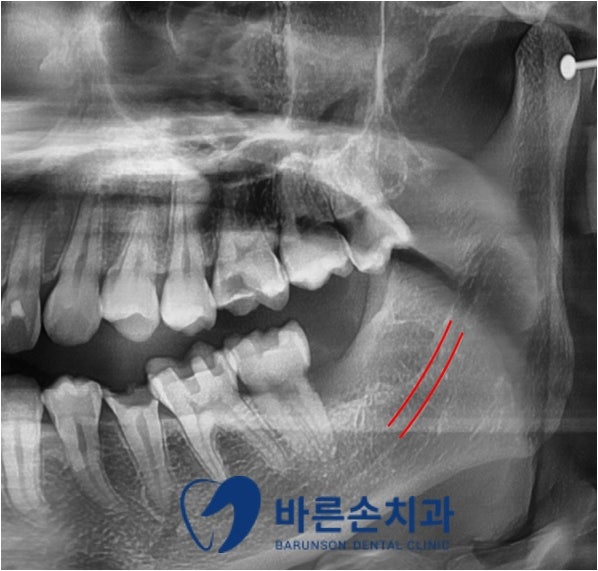

사랑니 발치 후 파노라마 사진입니다

잔존 치아나 하치조신경관의 손상 없이

사랑니가 깨끗하게 발치 된 것을 확인할 수 있습니다

하치조신경관의 손상이 발생할 경우 감각이상의 증상이 나타날 수 있으므로

신경관이 손상되지 않게 발치하는 것이 중요하죠!

또한 저희 치과에서는 발치 시 최소한의 절개로 진행하여

환자분의 불편감을 최대한 줄여드립니다^^